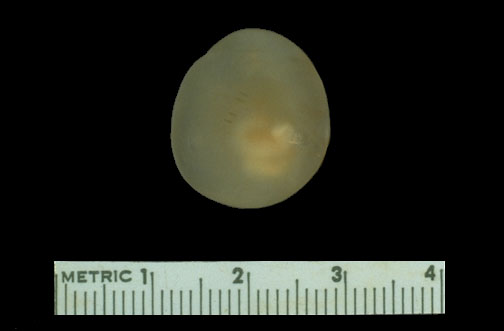

Here is the gross appearance of a cysticercus cyst that was removed from the brain.